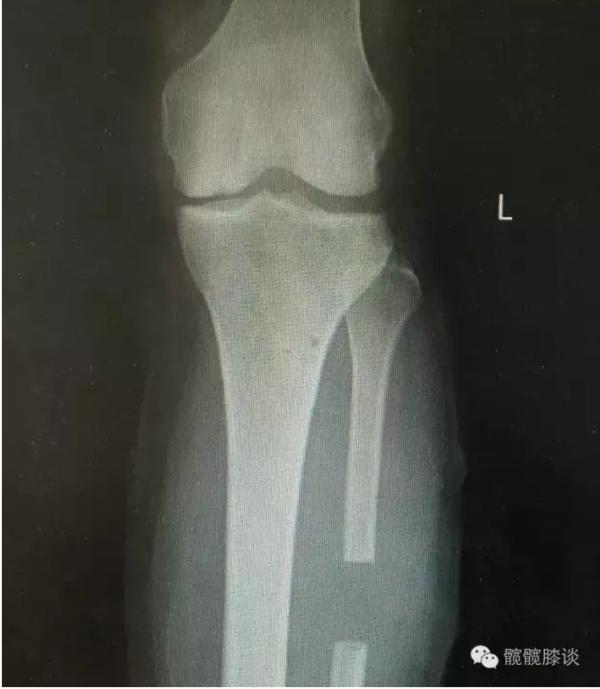

膝关节不均匀沉降术后患者X线片(下图)

术后图如下: